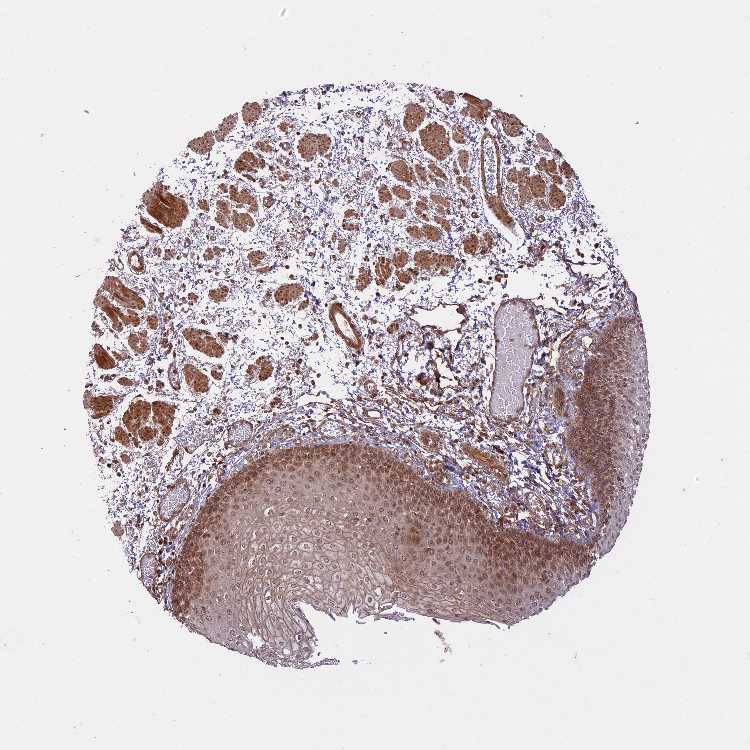

ESOPHAGUS - Antibody stainingi

Antibody staining in the annotated cell types in the current human tissue is reported as not detected, low, medium, or high, based on conventional immunohistochemistry profiling in selected tissues. This score is based on the combination of the staining intensity and fraction of stained cells.

Each image is clickable and will lead to virtual microscopy that enables deeper exploration of all samples and also displays staining intensity scores, fraction scores and subcellular localization as well as patient and tissue information for each sample.

Antibody HPA039533Antibody HPA040355

Squamous epithelial cells LowMedium